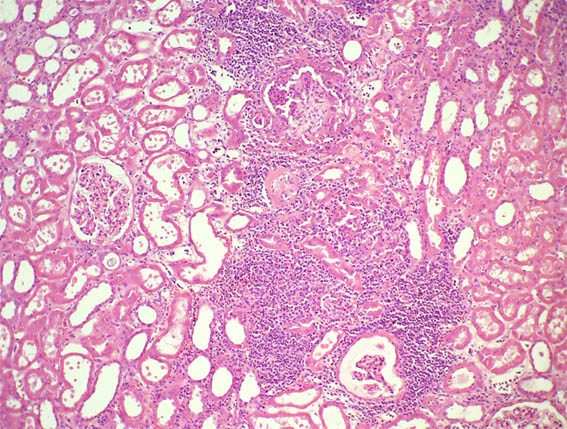

A renal open biopsy was performed. See the images:

Figure 1. H&E, X40.